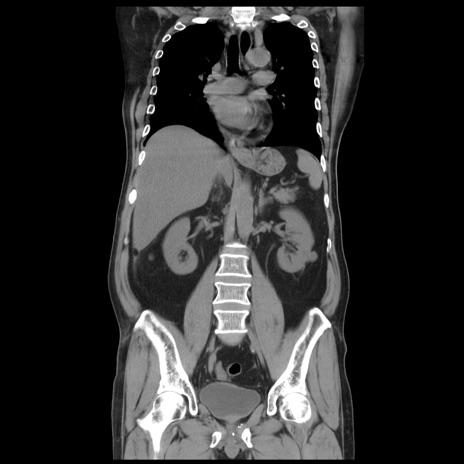

症例20(冠状断像)

【症例】 60歳代男性

【主訴】 腹部膨満、嘔吐

【現病歴】5日前頃より倦怠感を認め食事量減少し4日前の朝嘔吐、食事摂取困難となった。 3日前近医受診し点滴施行され整腸剤などを処方された。 当日他院を受診し、腹部膨満著明、炎症反応の上昇(CRP10.8、WBC11200)あり、紹介受診となる。

【身体所見】 意識JCS1 受け答えがはっきりしないBP 111/57mHg、 P 67bpm、、BT35.2°C、SpO2 97%(RA)、 腹部:膨隆、打診で鼓音あり、全体的に圧痛有り、腸蠕動音(-)、反跳痛ははっきりせず。

【データ】WBC 11400、CRP 14.20